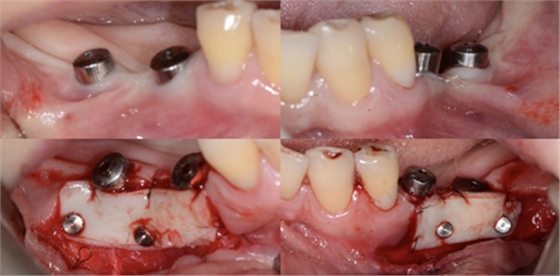

比如strip技術(shù),如下圖:

上圖中,種植體唇側(cè)缺乏附著齦,從上腭取瓣,常規(guī)做法:取長而寬的齦瓣,這樣供區(qū)面積大,術(shù)后疼痛重。

為了減少痛感,從雙側(cè)上腭取多條長而窄的齦瓣進(jìn)行移植,這樣每個供區(qū)的傷口都比較窄,可以減少術(shù)后的痛感。